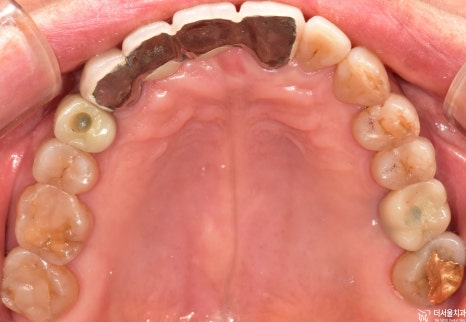

육안으로 살펴보았을때는

‘어? 어디가 문제라는거지?’

이렇게 생각할 수 있습니다.

근데 보여지는 것이 다가 아닙니다.

그 속에는 말 못할 상황이

벌어지고 있을 수 있습니다.

# 14, # 26 소구치 및 대구치에

치주염으로 인한 골소실이

나타난 것을 볼 수 있었습니다.

시커멓게 변해버린 곳이

이미 염증이 나타났었으며,

골소실이 일어난 것이죠.

그런데 그 정도는 이가 흔들릴 정도로

심했기에 이를 뽑을 수밖에 없었으며,

발치 후 임플란트 식립을 받으셔야 되었습니다.

파노라마와 육안으로 보여지듯

보철 수술은 무사히 잘 끝났습니다.